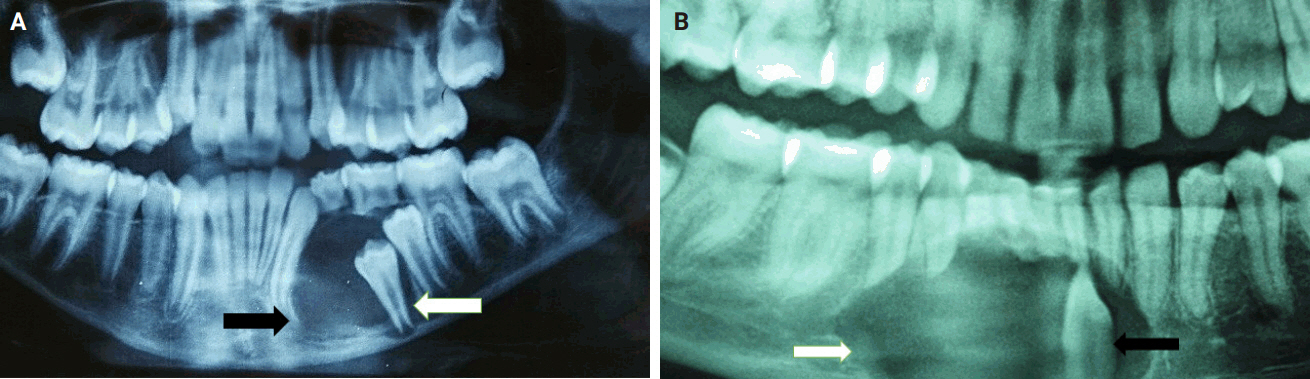

- Almost all cases exhibited typical histopathological findings of AOT: a solid growth pattern (n = 34), accompanied by ducts lined by cuboidal to low columnar epithelial cells proliferating in the form of whorls and nodules (n = 31). The ducts were filled with eosinophilic secretions in 31 cases, and interlacing strands or a lattice work pattern was seen in 30 cases. Psammomatous or dystrophic calcifications were seen in 31 cases. Other morphological findings included cystic areas (n = 20), CEOT-like areas (n = 13), ossifying fibroma-like areas (n = 6), fibrocollagenous stroma (n = 6), and associated osteodentin production (n = 6). Less frequent findings included mucin in ducts (n = 3), and in tubules (n = 7). Radiographically only six cases were associated with impacted teeth (Fig. 1A, B). The morphological features of AOT in relation to different tumor sites is presented in Table 2.

Fig. 1.Panoramic radiography demonstrating a well circumscribed unilocular lucent area in the left hemi mandible (black arrow) with thin sclerotic borders and impacted tooth on its left lateral aspect (white arrow) (A); a unilocular lucent area with thin sclerotic borders, wider than taller, occupying the symphyseal region and extending into the right parasymphyseal region (white arrow) associated with an impacted tooth in vertical orientation (black arrow) (B).